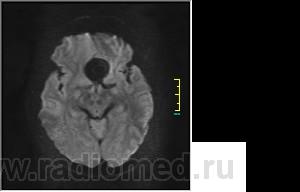

Ax T2 Flair:

DWI:

частично функционирующая аневризма

Иначе говоря, аневризма с хронической геморрагией, т.к. мы видим фракции крови различного возраста.

По-моему, аневризма с пристеночными тромбами.

Постепенное пристеночное образование тромбов приводит к появлению типичного для аневризмы феномена -слоистости МР сигнала в полости аневризмы. Данная картина демонстрирует слоистый характер тромботических масс в полости аневризмы .Функционрирующая часть имеет низкий сигнал во всех режимах сканирования. Дополнительно-перифокальный отек.

А может более корректно интерпретировать как частично тромбированная аневризма... Уж коь речь идет о фракциях, ну то есть о тромбе по сути.... Ну и плюс перфокальный отек головного мозга (вероятнее цитотоксический+вазогенный).